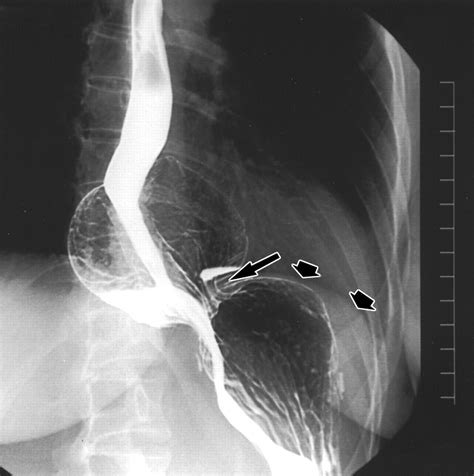

• picture of nissen fundoplication